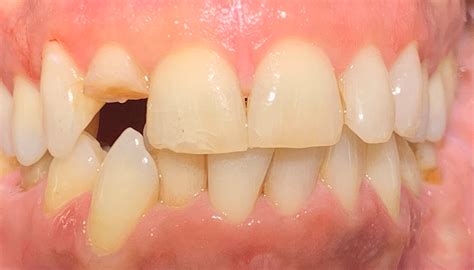

A major concern for patients is whether a root canal on front tooth will cause the tooth to turn dark or gray over time. While this can happen due to internal debris or the material used, modern techniques have significantly reduced the risk. If color changes do occur, your dentist can suggest cosmetic solutions such as internal bleaching, porcelain veneers, or a crown to match your natural tooth shade.

• Discoloration or darkening of the tooth.